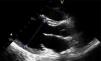

Case reportA 14-year-old girl with a history of hemiplegic migraine and pineal cyst was admitted for control brain magnetic resonance imaging (MRI). During anesthesia induction with propofol she suffered bradycardia, which was reversed with atropine, followed by ventricular tachyarrhythmia, reversed with lidocaine and precordial thump. Within hours she developed pulmonary edema (Figure 1) and global respiratory failure (PaO2/FiO2 156, pCO2 57 mmHg) and hypotension (systolic/diastolic blood pressure 89/56 mmHg). The transthoracic echocardiogram showed a dilated left ventricle with global hypokinesia of the mid and basal segments but sparing the apex, resulting in moderate to severe impairment of left ventricular global systolic function and reduced ejection fraction (<30%) (Figures 2 and 3). The electrocardiogram (ECG) showed persistent sinus tachycardia and nonspecific ST-T wave abnormalities in V4 and V5 (Figure 4). Cardiac biomarkers were elevated (total creatine kinase [CK] 217 UI/l, troponin I 2.42 ng/ml and pro-brain natriuretic peptide [proBNP] 8284 pg/ml). The patient was placed on diuretics and captopril, with dopamine to optimize renal function (maximum 2 μg/kg/min) and digoxin in the first 24 h.

TTS may present echocardiographically in the classical form (with apical ballooning and involvement of the apical or mid-apical segments) or the inverted form (with involvement of the mid, basal or mid-basal segments).3 The case presented was of the inverted or global form, both reported at pediatric ages.3